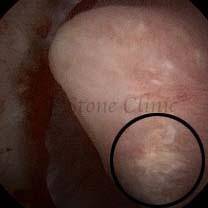

These images are taken as snap shots from the video recording of RIRS Surgery done at our hospital. These are Randall’s Plaques seen with Digital FLEX XC & Digital FLEX XC S. The cream or whitish patches are seen on the tips of RENAL PAPILLAE as seen in images below.

The Below Images Show Small Stones attached to the Renal Papillae.